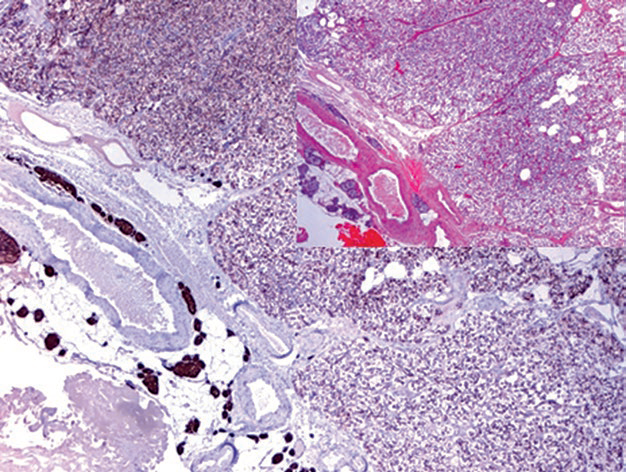

图3. 甲状旁腺腺瘤及受挤压的甲状旁腺均表达GATA-3(左)及Pax-8(右)。

图4. 甲状旁腺腺瘤及正常甲状旁腺组织中,均为PTH阳性表达。